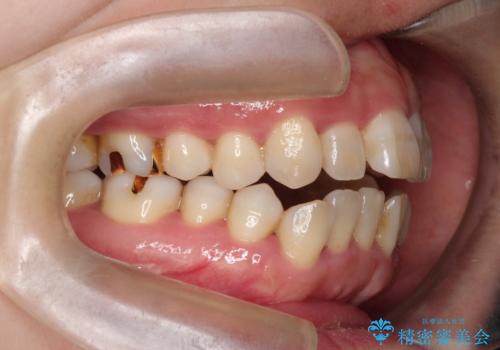

- 上下の前歯の開き(開咬)と上下前歯にガタつき(叢生)が見られます。

マウスピース矯正ではメカニクス的に開咬へのアプローチが容易です。

インビザラインの特色を生かした歯牙移動計画を作成し、非抜歯にて治療を行いました。